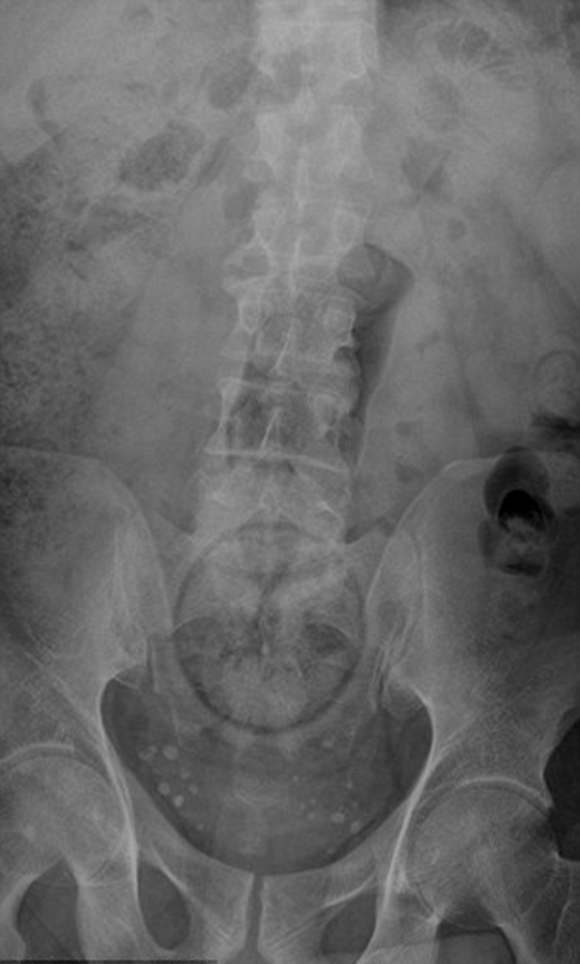

▼塞了聖誕糖果。